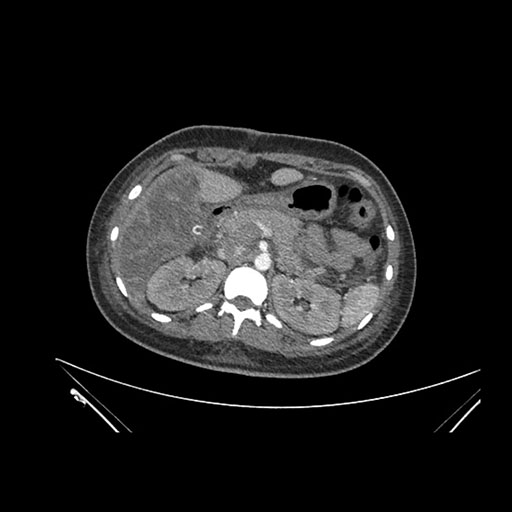

Imaging Analysis

Look through the patient's CT scan to identify any areas of concern for the necessary procedure.

Axial Arterial

Axial Venous